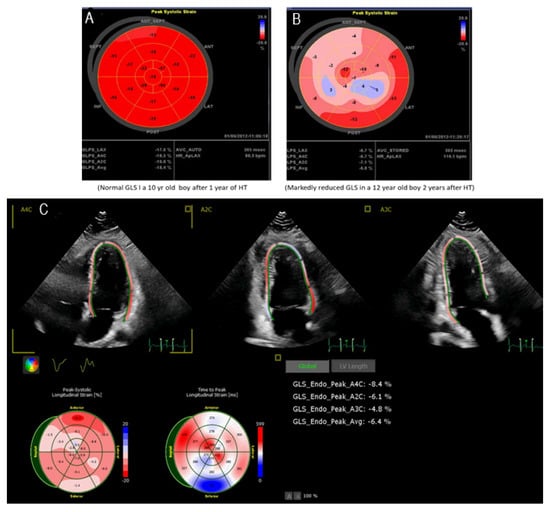

Left ventricle ejection fraction (LVEF) and fractional shortening (LVFS) are standard methods of quantifying LV systolic function. However, after HT, altered geometry of ventricles, resting tachycardia, and abnormal septal motion occur, making standard echocardiography less sensitive to detect early dysfunction, rejection, or CAV. Strain and strain rate analysis allows quantifying myocardial function at the regional level. STE is a more precise method for quantifying LV function in pediatrics, with lower variability than LVEF and LVFS [22]. Calculating strain and strain rate by 2-D STE in children has also been shown to correlate with LVEDP [23,24,25]. Global longitudinal strain (GLS) is the most common strain analysis used in pediatric HT recipients. Several small studies found that noninvasive GLS is sensitive and specific in identifying acute clinical rejection in pediatric HT recipients [6,26,27,28,29]. Speckle tracking strain and strain rate imaging were also helpful in defining low-grade rejection in children after HT [30]. GLS by speckle tracking echocardiography imaging correlates better with invasive measurement of LVEDP than traditional echocardiographic parameters [31,32]. The STE strain imaging is also valuable for detecting the early development of CAV in children after HT [33]. An example of 2-D speckle tracking imagine differentiating no-rejection versus chronic rejection in a pediatric HT recipient is shown in Figure 3A–C. The advantage of STE is higher spatial resolution and is angle independent. The disadvantages are similar to TDI, no normal values are established in pediatric HT recipients, and there is a learning curve for this modality among technicians and physicians.

Figure 3. (A) Normal global longitudinal strain, (B) Markedly decreased global longitudinal strain; and (C): Average of global longitudinal strain, markedly decreased in a 15-year-old boy after 2 years of HT.